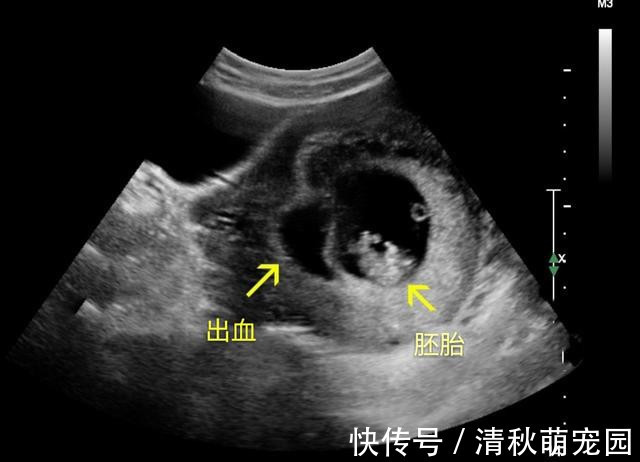

情况三:怀孕12周产检B超一般做B超看到胎儿的胎心后,一直到12周之前,就不用再检查了,孕妈在家好好养胎即可。除非中间 出现了意外情况,如有出血、剧烈腹痛等,有这些表现要及时去看医生。

文章插图